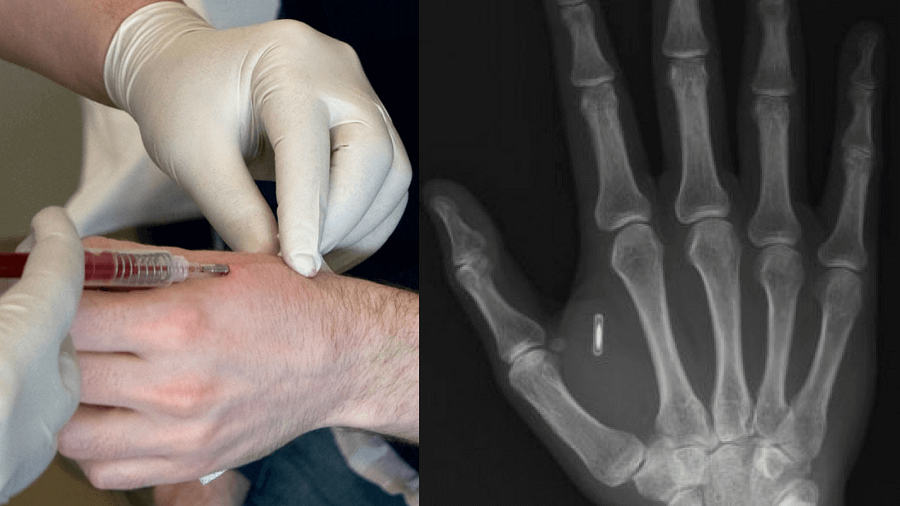

خبرگزاری علم و فناوری آنا، هدا عربشاهی؛ امروزه بیشتر مردم با مفهوم ریزتراشهها آشنا هستند. این دستگاههای کوچک در تلفنهای همراه و رایانهها و حتی در حیوانات تعبیه میشوند اما ادغام این فناوری با زیستشناسی انسان فکری است که پذیرش آن هنوز برای بسیاری از مردم آسان نیست. هرچند بهنظر میرسد که ظرف دهههای آینده بیشتر مردم جهان به این فناوری مجهز شوند. مفهوم ریزتراشه انسانی نسبتا ساده است و کاشت مدارهای مجتمع میکروسکوپی زیر پوست انسان، معمولا در فاصله میان انگشت شست و انگشت سبابه را شامل میشود. این تراشهها میتوانند اهداف مختلفی ازجمله تشخیص هویت، پرداختهای با دست و موارد دیگر را انجام دهند. ریزتراشه کاشتی انسانی علاوهبر مدارمجتمع میتواند به یک فرستنده RFID (سامانه بازشناسی با امواج رادیویی) مجهز باشد که درون یک قاب شیشهای سیلیکاتی محصور و در بدن انسان کاشته میشود. این نوع ایمپلنت زیرپوستی معمولاً حاوی یک شمارهشناسایی منحصربهفرد است که به دادههای موجود در پایگاه دادههای بیرونی چون مرکز تشخیص هویت، اجرای احکام، تاریخچه پزشکی، داروها، آلرژیها و اطلاعات تماس متصل میشود.

امروزه، بیشاز ۵۰هزار نفر در دنیا انتخاب کردهاند که ازطریق جراحی، تراشهای زیر پوستی را بین انگشت شست و انگشت سبابه بگذارند و باکمک این تراشه از دست خود بهعنوان کلیدهای خانه یا کارت اعتباری استفاده کنند. برایمثال، در آلمان بیشاز ۲هزار نفر برای دریافت این ایمپلنتها انتخاب شدهاند و حتی مردی آلمانی از این دستگاه برای ذخیره وصیتنامهاش استفاده کرد.